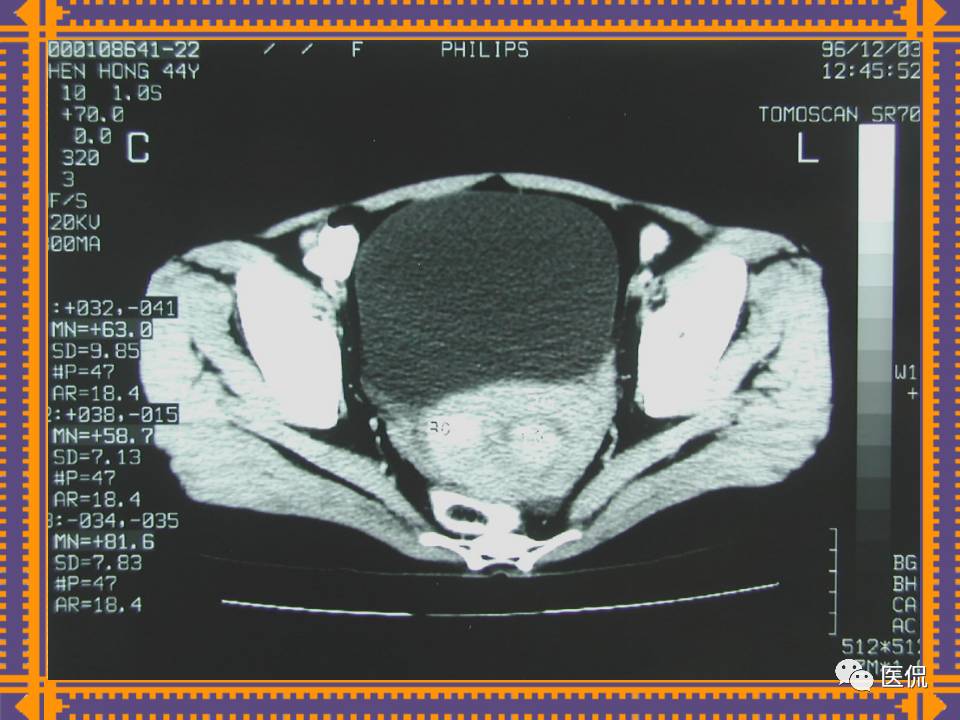

这篇PPT对男性生殖系统疾病:前列腺增生、前列腺癌;女性生殖系统疾病:子宫肌瘤、子宫癌、卵巢囊肿和卵巢肿瘤以及腹膜后间隙疾病进行了详细讲解。